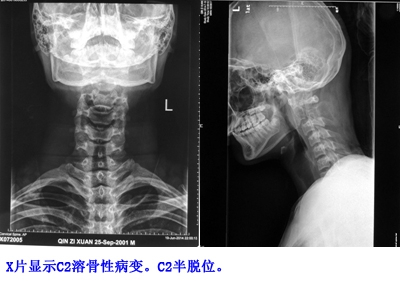

患者2个月前在颈部轻微外伤后出现枕颈部疼痛。2周后出现发热,最高38.3°C,经对症治疗2周后体温恢复正常。但颈痛逐渐加重,发展到起床后必须用双手支撑头部。外院行X片检查发现C2破坏性病变。来我院后,于门诊行CT引导下穿刺活检,病理检查提示“神经外胚叶肿瘤(PNET)”。在等待病理过程中,患者出现手指麻木,下肢无力。大小便正常。

患者C2 PNET诊断明确。目前患者颈痛严重,VAS评分9分。C2溶骨性破坏,国际脊柱肿瘤研究小组稳定性评分13分(不稳定)。肿瘤侵入椎管造成脊髓压迫,开始出现神经功能障碍。决定先行手术切除肿瘤、稳定脊柱、缓解神经功能。术后全身化疗及局部放疗。